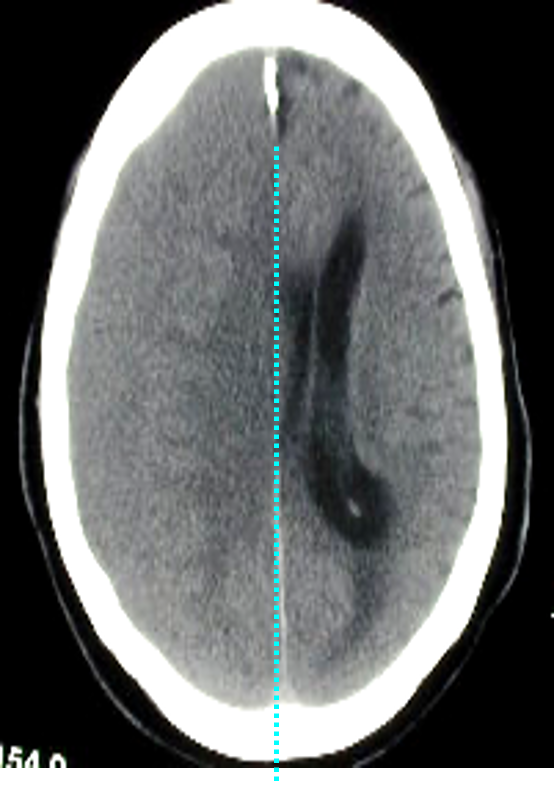

Mass effect

- Effacement of the cortical sulci

- Compression of the ventricle

- Shift of the midline structures

- Transtentorial brain herniation